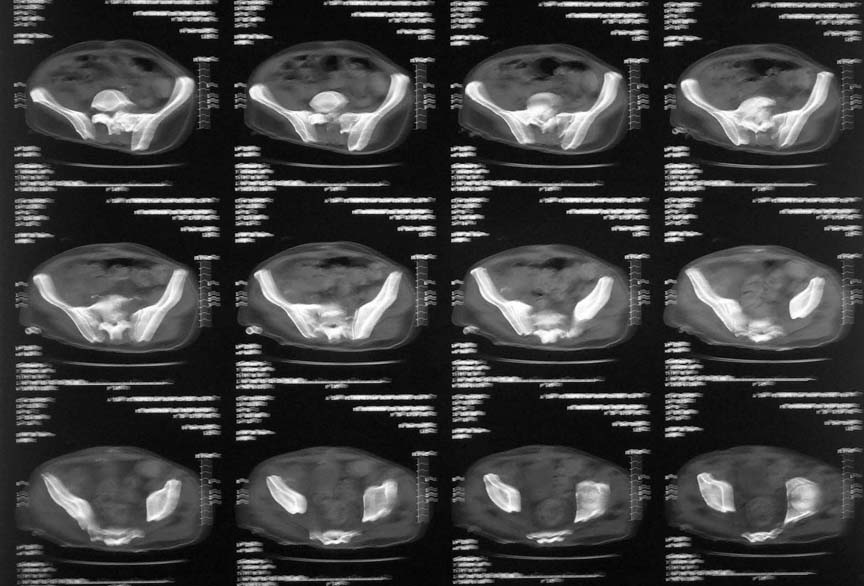

65 year old male patient was allegedly injured in a railway accident two months ago. He was treated till recently elswhere and has now been transferred to our centre. Had suffered pelvic ring injury and urinary bladder injury. Was treated with lower abdominal laparotomy, bladder repair and an SPC. No active treatment was done for the bony injuries.

In our centre we found that there is an unstable pelvis which could be compressed and distracted. bilateral acetabular injury with central fracture on the right side - femoral head partially caught in the floor of acetabulum, left side femoral head located, sacral fracture with ant body comminution etc, a suprapubic urinary catheter with wound infection, a bed sore over the left gluteal region etc. Our urologist was able to convert the bladder drainage to an urethral catheter. The right femoral head could be pulled out of the floor of the acetabulum and reduction retained on axial skeletal traction. The anterior pelvic ring has been stabilised on external fixator. Small rotation flap was done for the left gluteal pressure sore and is healing.

I think your plan is okay. His femoral head damage looks horrible in the film you attached. He's likely to develop arthritis in the future - you may be smart to avoid hardware and surgery with a hip like that.